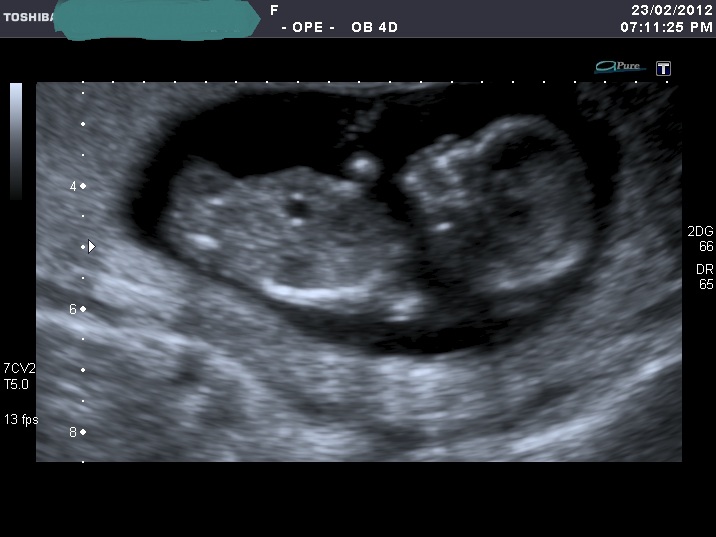

I'm sorry for spaming again with my nub shots, but now when I look at u/s pics I'm not sure I can a see a nub at all????

If you can see it, please enlighten me where to look. Also I think scull looks girly on some pics and boyish on the others.

I was 12 weeks, measuring 12 weeks 5 days